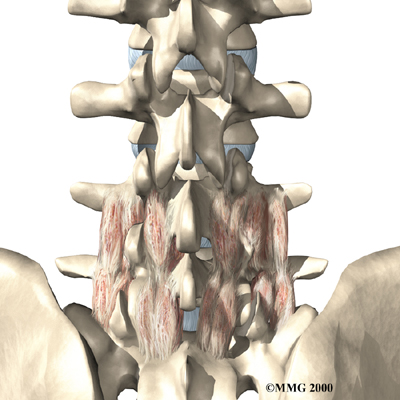

Posterior Lumbar Fusion

Lumbar disc herniation causes mechanical pain, the type of pain caused by wear and tear in the parts of the lumbar spine. Fusion surgery is mainly used to stop movement of the painful area by joining two or more vertebrae into one solid bone. This keeps the bones and joints from moving, easing mechanical pain.

In posterior lumbar fusion, the surgeon lays small grafts of bone over the problem area on the back of the spinal column. Most surgeons will also apply metal plates and screws to prevent the problem vertebrae from moving. This protects the graft so it can heal better and faster.